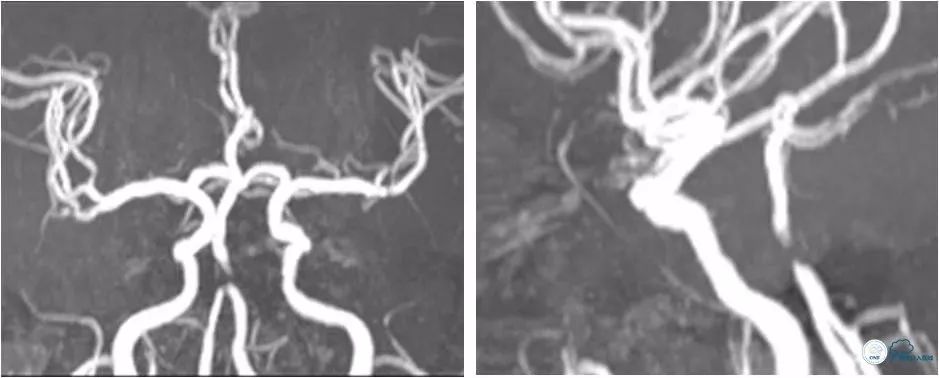

MRA:双侧椎动脉V4段-基底动脉重度狭窄(图2)。

图2

颅内CTA(2018-7-9):双侧椎动脉V4段-基底动脉重度狭窄(图4)。

图4